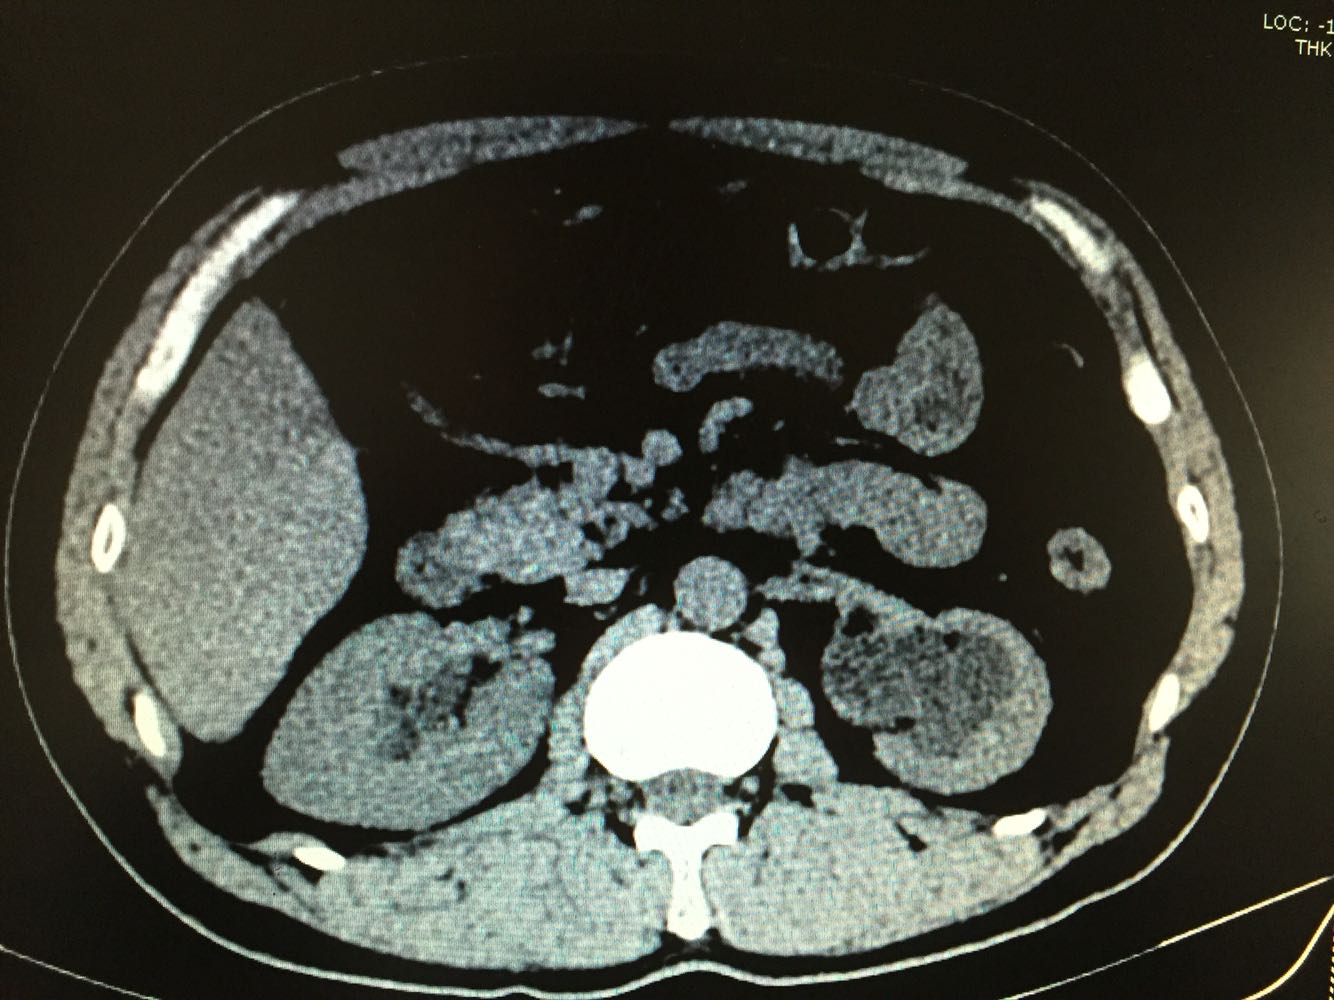

双侧输尿管结石

体检发现双侧输尿管结石,双肾积水1周,尿量无明显变化

双侧输尿管结石,双肾积水

治疗方案,拟先行左侧输尿管镜下碎石,再行右侧输尿管软镜下碎石术。